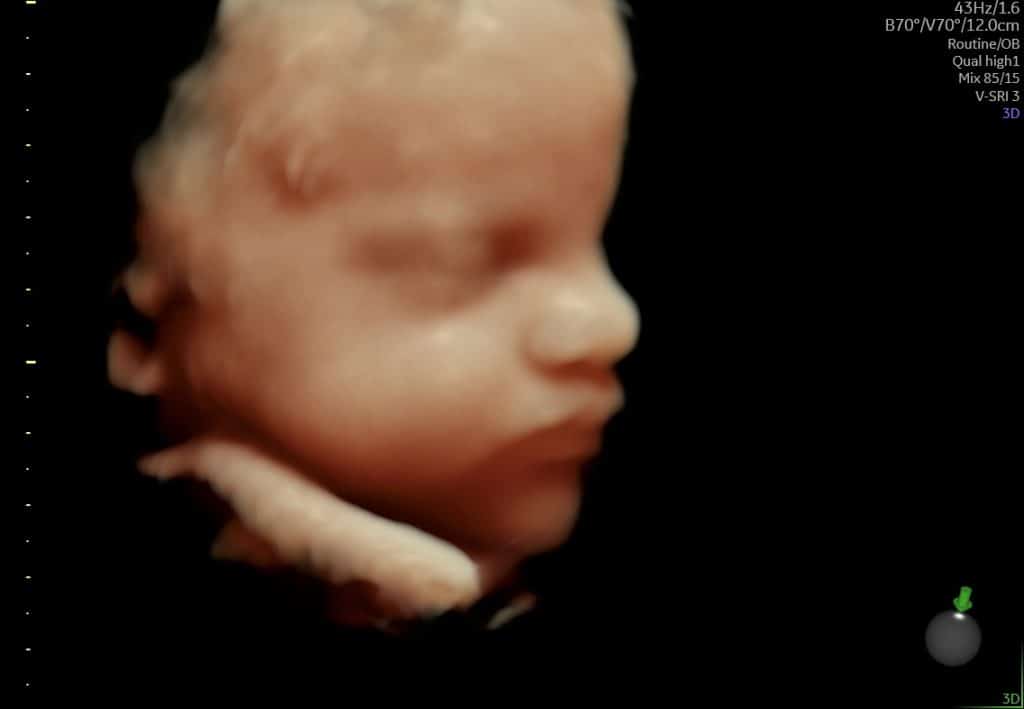

Ultralydsscanning uge 30 – ansigt i profil

3D scannning uge 30 – baby ansigt

Ultralyd i sen graviditet. Det er normalt, at man kun ser dele af barnet ad gangen.

3D-ultralyd omkring uge 30 giver ofte et første indtryk af barnets ansigtstræk. Kinder, næse og mund kan være synlige, men billedets udtryk afhænger i høj grad af barnets stilling og pladsforholdene i livmoderen.